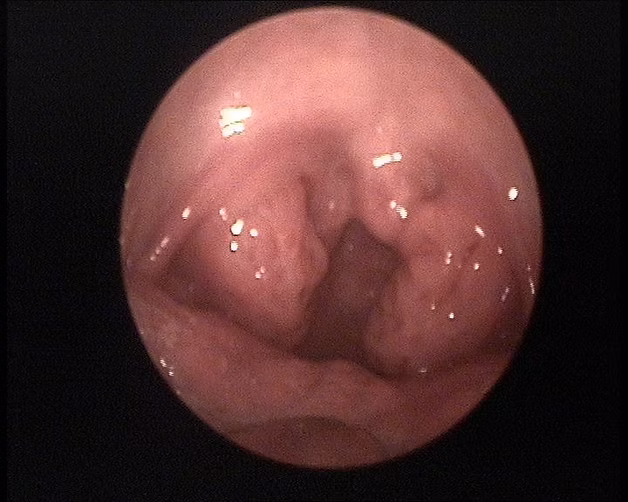

Antes - Amígdalas hipertróficas

Después - Amígdalas extirpadas

Se observa la fosa amigdalar limpia. el paciente mejora su estado general y su respiración nocturna.